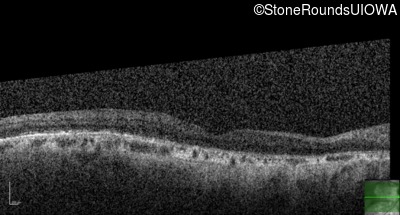

Optical Coherence Tomography - Left - 20/200

Exemplar / OCT Stack